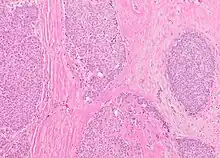

The microscopic histopathology of typical PDCIS lesions (refer to adjacent high-power photomicrograph) prepared with a hematoxylin and eosin stain consists of mammary ducts that have papillary fronds (i.e. thin, finger-like or leaf-like structures) lined with one or several layers of neoplastic, columnar-shaped epithelial cells (i.e. tall, narrow cells with their nuclei close to the site of their ductal attachment).[4] The fronds have branching fibrovascular cores. Epithelial cells lining the fronds' inner surfaces commonly form solid, cribriform (i.e. large nests of cells perforated by many rounded, variably sized spaces), or micro-papillary patterns. There may be a second population of epithelial cells lining the papillae that have abundant clear cytoplasm in addition to the usual neoplastic epithelial cells which line the papillae. These cells, which are not myoepithelial cells, have been termed globoid cells.[7] They have eosinophilic cytoplasm (i.e. pink or red cytoplasm due to its uptake of eosin stain).[6] PDCIS tumors with these cells have been termed dimorphic variants of PDCIS.[3] Myoepithelial cells are typically present at the periphery of the fronds but absent within the involved ducts.[4][7] The presence of a fibrous capsule and/or absence of peripherally located myoepithelial cells are strong indicators that the tumor is an ESP rather than a PDCIS.[3] PDCIS tissues may also contain areas of "Comedo-type necrosis", i.e. areas where dead cells have accumulated.[6]

Microscopic histopathological analyses of SPC lesions (refer to adjacent high-power photomicrograph) generally show tumors with multiple circumscribed nodules of expanded ducts filled with neoplastic epithelial cells which may appear spindle-shaped or plasma cell-like, have red to pink cytoplasm due to the uptake of eosin after staining with hematoxilin & eosin, and eccentrically-placed nuclei. Rarely, signet ring-shaped cells are present. The tumors may have cystic and hemorrhagic areas. Myoepithelial cells are found within and at the periphery of these tumors. The papillary architecture seen in the other SCB types is in general not apparent; rather, pseudo-rosettes (i.e. radial arrangements of neoplastic cells around small blood vessel) and nuclear palisading (i.e. parallel arrangements of the nuclei in rows of tumors that resembles picket fences) around stromal cores (i.e. supporting tissues) may be seen. SPC tumor tissues typically (>50% of cases) have areas of neuroendocrine differentiation. The presence of these areas strongly supports the diagnosis of SPC.[21] The signet ring-shaped cells in these tumors contain cytoplasmic mucin-containing vacuoles which push their cells' nuclei to one side.[10] Mucin may also occur outside of cells in these lesions. The presence of signet ring-shaped cells bearing mucin-containing vacuoles with or without extracellular mucin strongly supports the diagnosis of SPC. SPC is considered invasive when the tumor nests have a characteristic jigsaw growth pattern with ragged and irregular margins with the loss of myoepithelial cells at the site(s) of invasion.[21] Rarely, invasive SPC occurs with nearby invasive carcinoma of NST, lobular carcinoma, cribriform carcinoma, or tubular carcinoma breast tumors.[3]